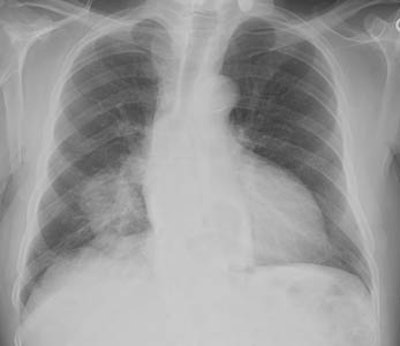

Hypertrophic osteoarthropathy: The patient shown below was being evaluated for bone pain. The bone scan revealed patchy, linear tracer uptake along the femurs, tibias, and distal upper extremitis (black arrows). A plain film reveal a solid periosteal reaction. CXR demonstrated a large right lung mass. |